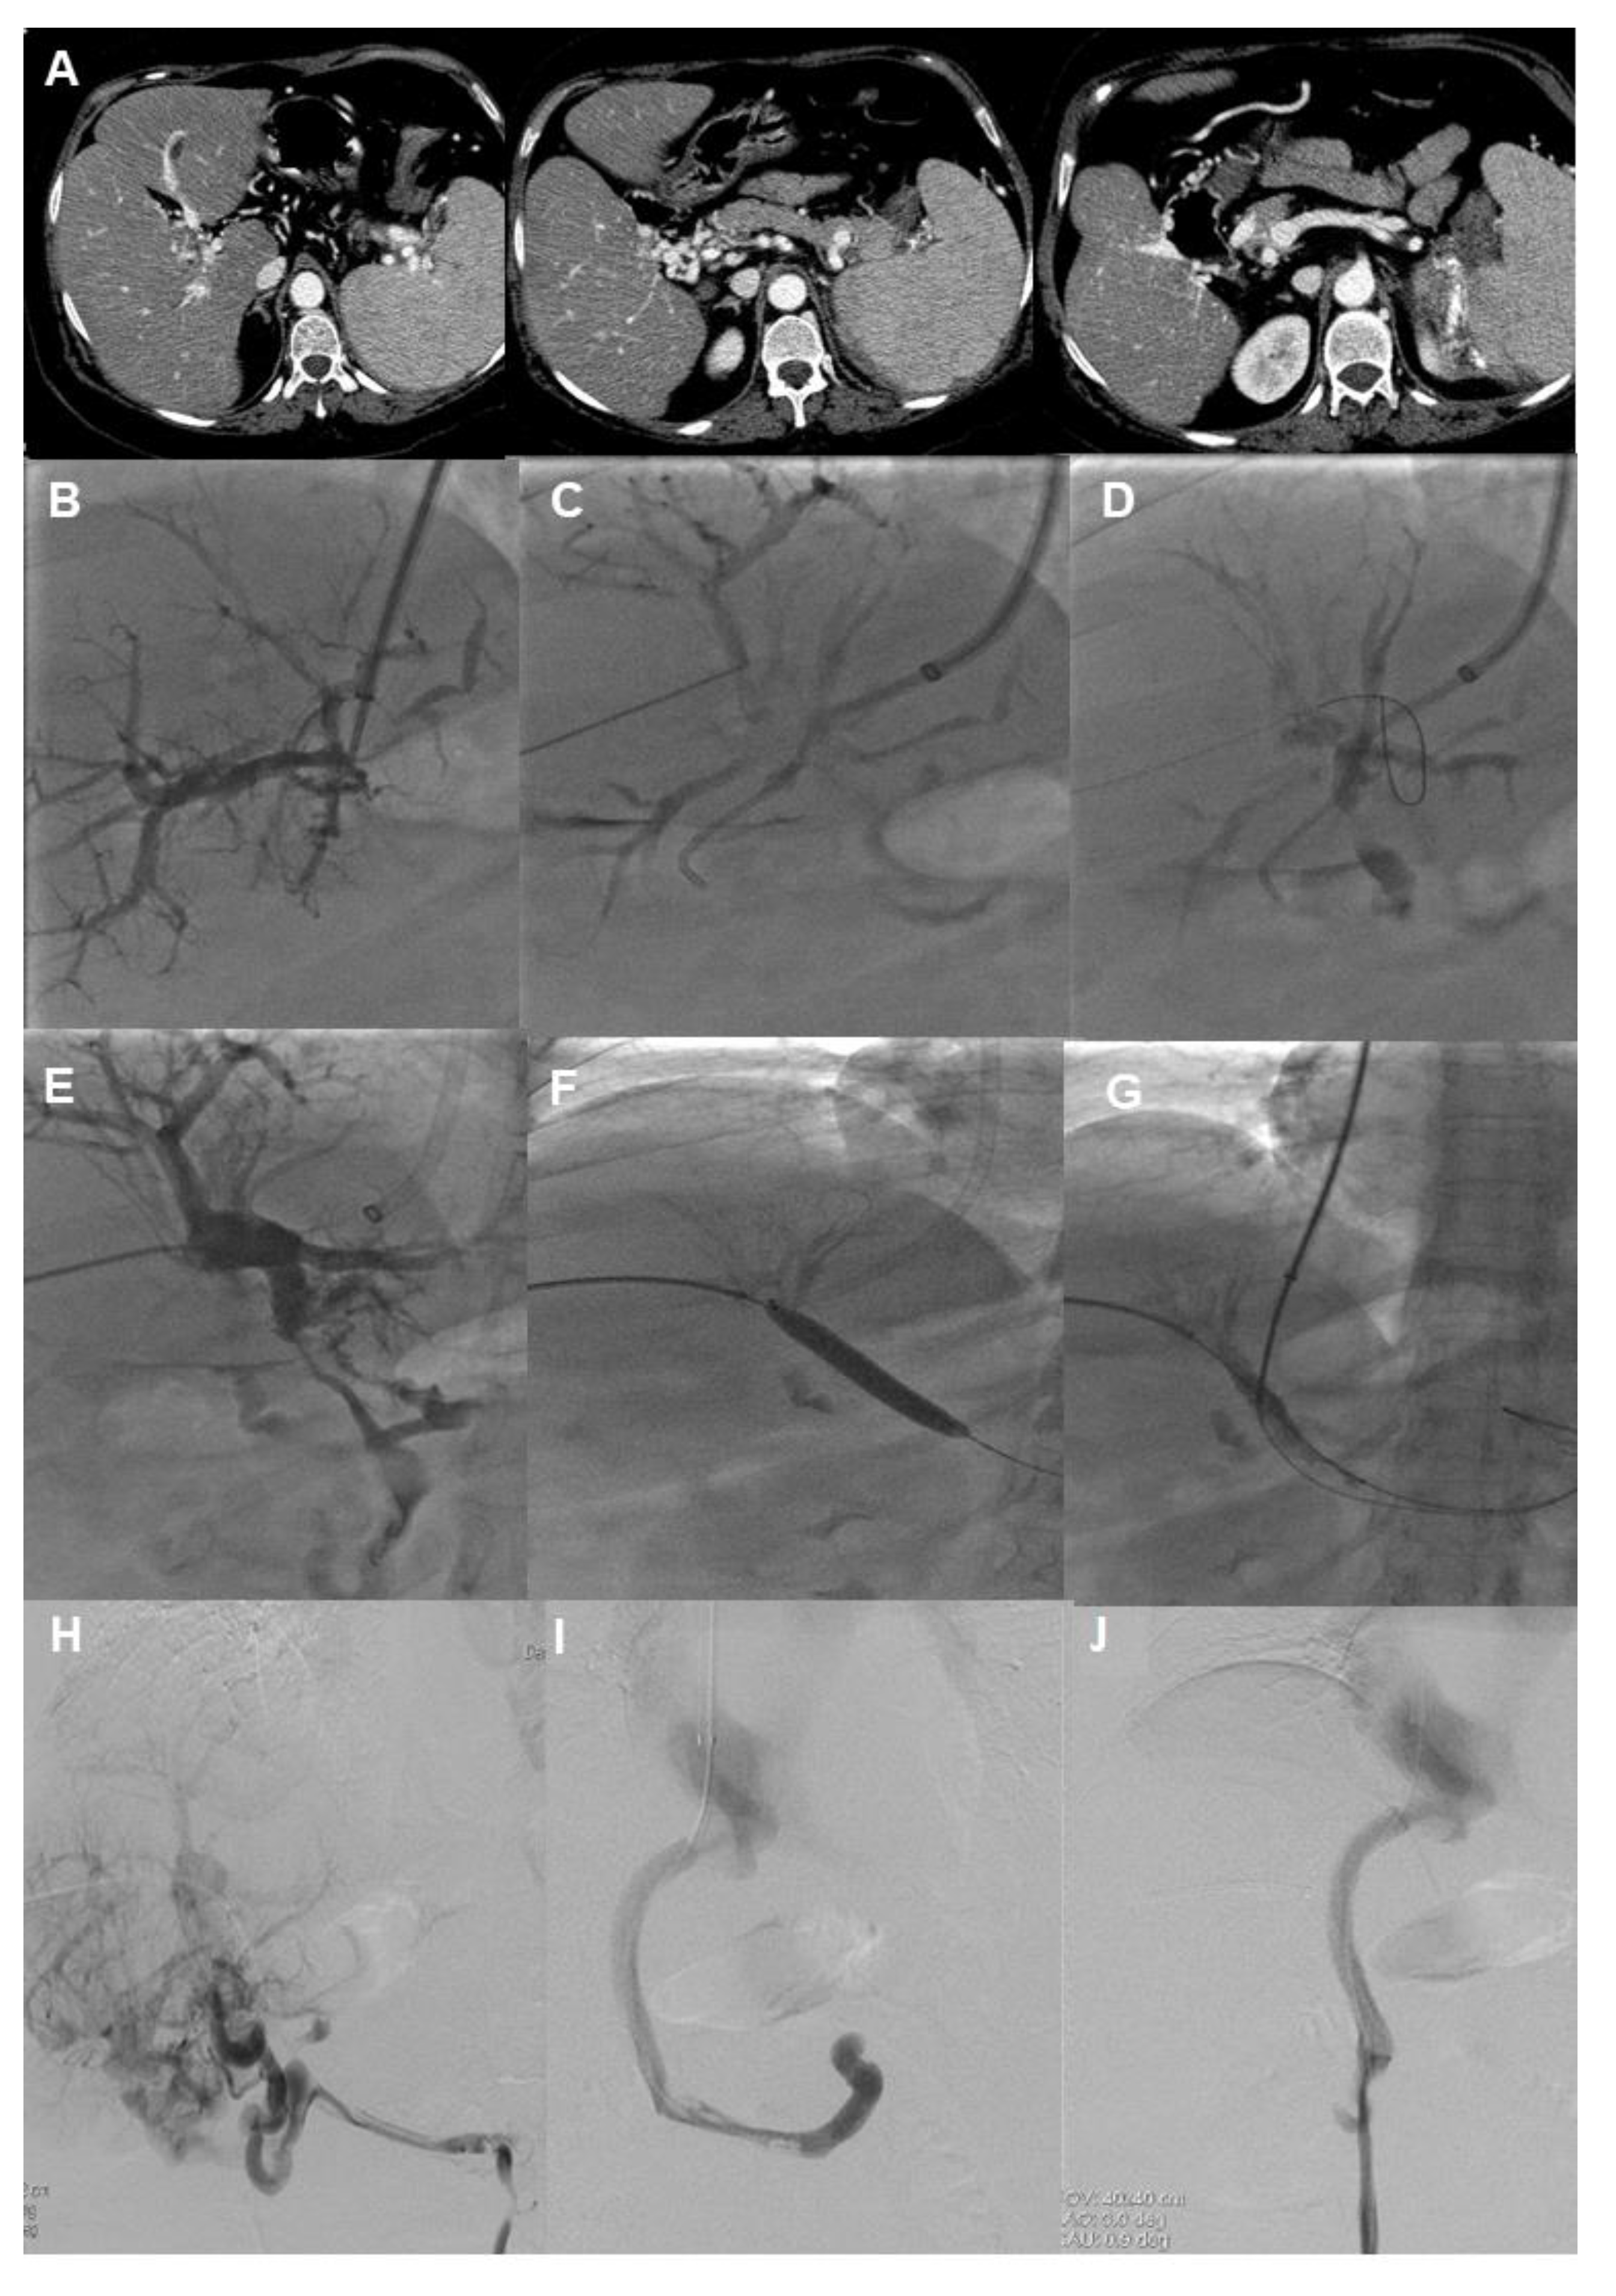

- Klinger, C.; Riecken, B.; Schmidt, A.; De Gottardi, A.; Meier, B.; Bosch, J.; Caca, K. Transjugular portal vein recanalization with creation of intrahepatic portosystemic shunt (PVR-TIPS) in patients with chronic non-cirrhotic, non-malignant portal vein thrombosis. Z. Gastroenterol. 2018, 56, 221–237. [Google Scholar] [CrossRef]

- Knight, G.M.; Clark, J.; Boike, J.R.; Maddur, H.; Ganger, D.R.; Talwar, A.; Riaz, A.; Desai, K.; Mouli, S.; Hohlastos, E.; et al. TIPS for Adults Without Cirrhosis With Chronic Mesenteric Venous Thrombosis and EHPVO Refractory to Standard-of-Care Therapy. Hepatology 2021, 74, 2735–2744. [Google Scholar] [CrossRef]

- Qi, X.; Han, G.; Yin, Z.; He, C.; Wang, J.; Guo, W.; Niu, J.; Zhang, W.; Bai, M.; Fan, D. Transjugular intrahepatic portosystemic shunt for portal cavernoma with symptomatic portal hypertension in non-cirrhotic patients. Dig. Dis. Sci. 2012, 57, 1072–1082. [Google Scholar] [CrossRef]

- Rosenqvist, K.; Eriksson, L.G.; Rorsman, F.; Sangfelt, P.; Nyman, R. Endovascular treatment of acute and chronic portal vein thrombosis in patients with cirrhotic and non-cirrhotic liver. Acta Radiol. 2016, 57, 572–579. [Google Scholar] [CrossRef]

- Senzolo, M.; Tibbals, J.; Cholongitas, E.; Triantos, C.K.; Burroughs, A.K.; Patch, D. Transjugular intrahepatic portosystemic shunt for portal vein thrombosis with and without cavernous transformation. Aliment. Pharmacol. Ther. 2006, 23, 767–775. [Google Scholar] [CrossRef]

- Buechter, M.; Manka, P.; Gerken, G.; Canbay, A.; Blomeyer, S.; Wetter, A.; Altenbernd, J.; Kahraman, A.; Theysohn, J.M. Transjugular Intrahepatic Portosystemic Shunt in Patients with Portal Hypertension: Patency Depends on Coverage and Interventionalist’s Experience. Dig. Dis. 2018, 36, 218–227. [Google Scholar] [CrossRef]

- Hernandez-Gea, V.; Bureau, C. Practice makes better: TIPS procedures in referral centers. Hepatology 2018, 67, 473–475. [Google Scholar] [CrossRef]